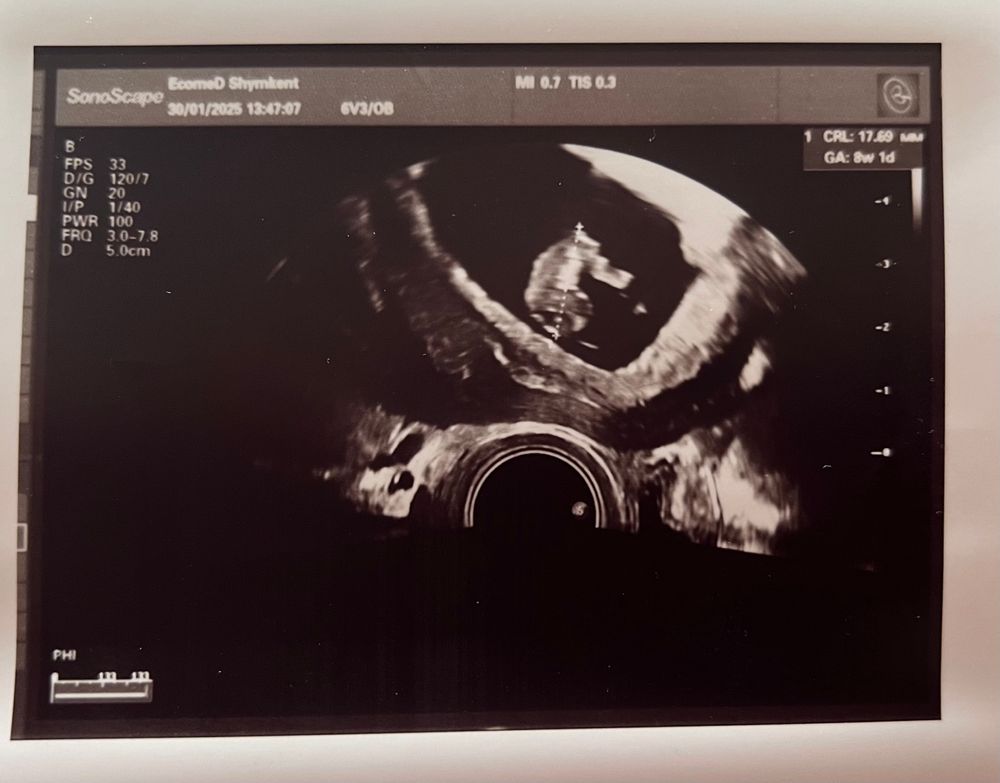

Сходила вчера 30.01 на сроке 8,2

СВД-38мм

КТР-17,6мм

ЖМ-5мм

СБ+167

Между плодный яйцом и стенкой матки лоцируется гипоэхогенный участок 14мм, беременность 8,1